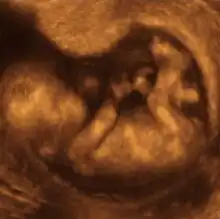

- Ultrassonografia

A ultrassonografia médica, também conhecida como ecografia, usa ondas sonoras de alta frequência para criar imagens do interior do corpo. A máquina de ultra-som envia ondas sonoras para o corpo e é capaz de converter os ecos de som de retorno em uma imagem. A tecnologia de ultra-som também pode produzir sons audíveis de fluxo sanguíneo, permitindo que os profissionais médicos usem sons e imagens para avaliar a saúde do paciente. O ultra-som é frequentemente utilizado para avaliar:

- Gravidez;